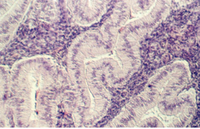

Stratified Cuboidal

Sweat gland ducts are examples of stratified cuboidal epithelium...usually however there are only two layers of cells. They can be found in your slide 25 (thick skin), in the dermis.